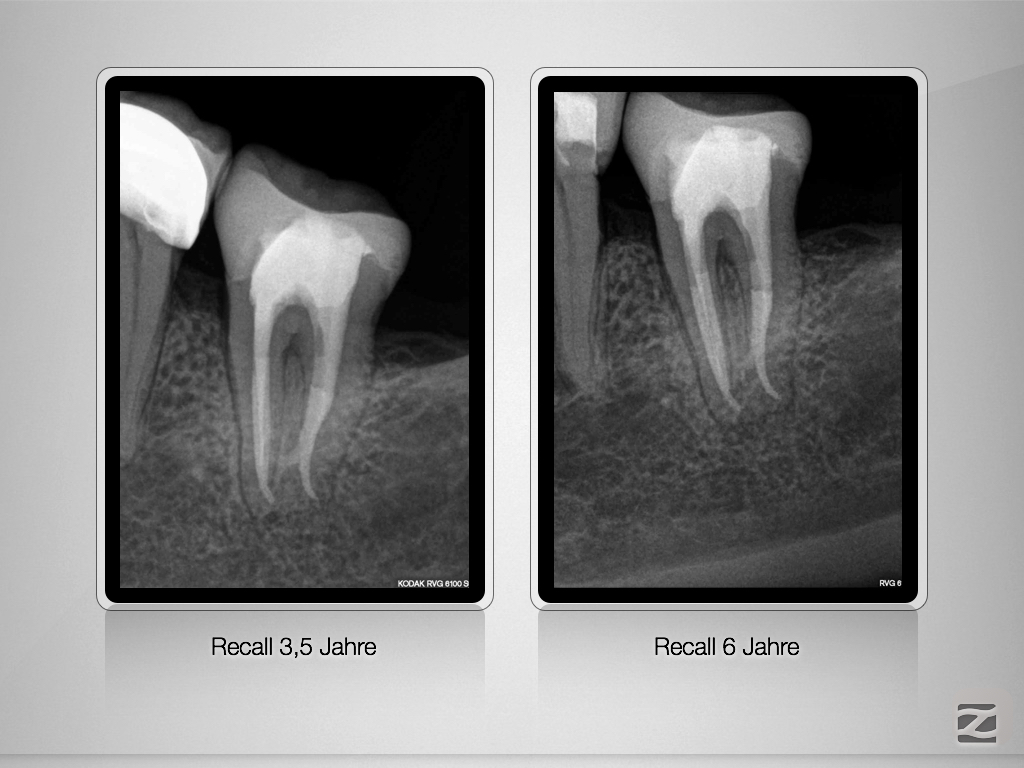

37D.005

X-Bein mit Kommunikation